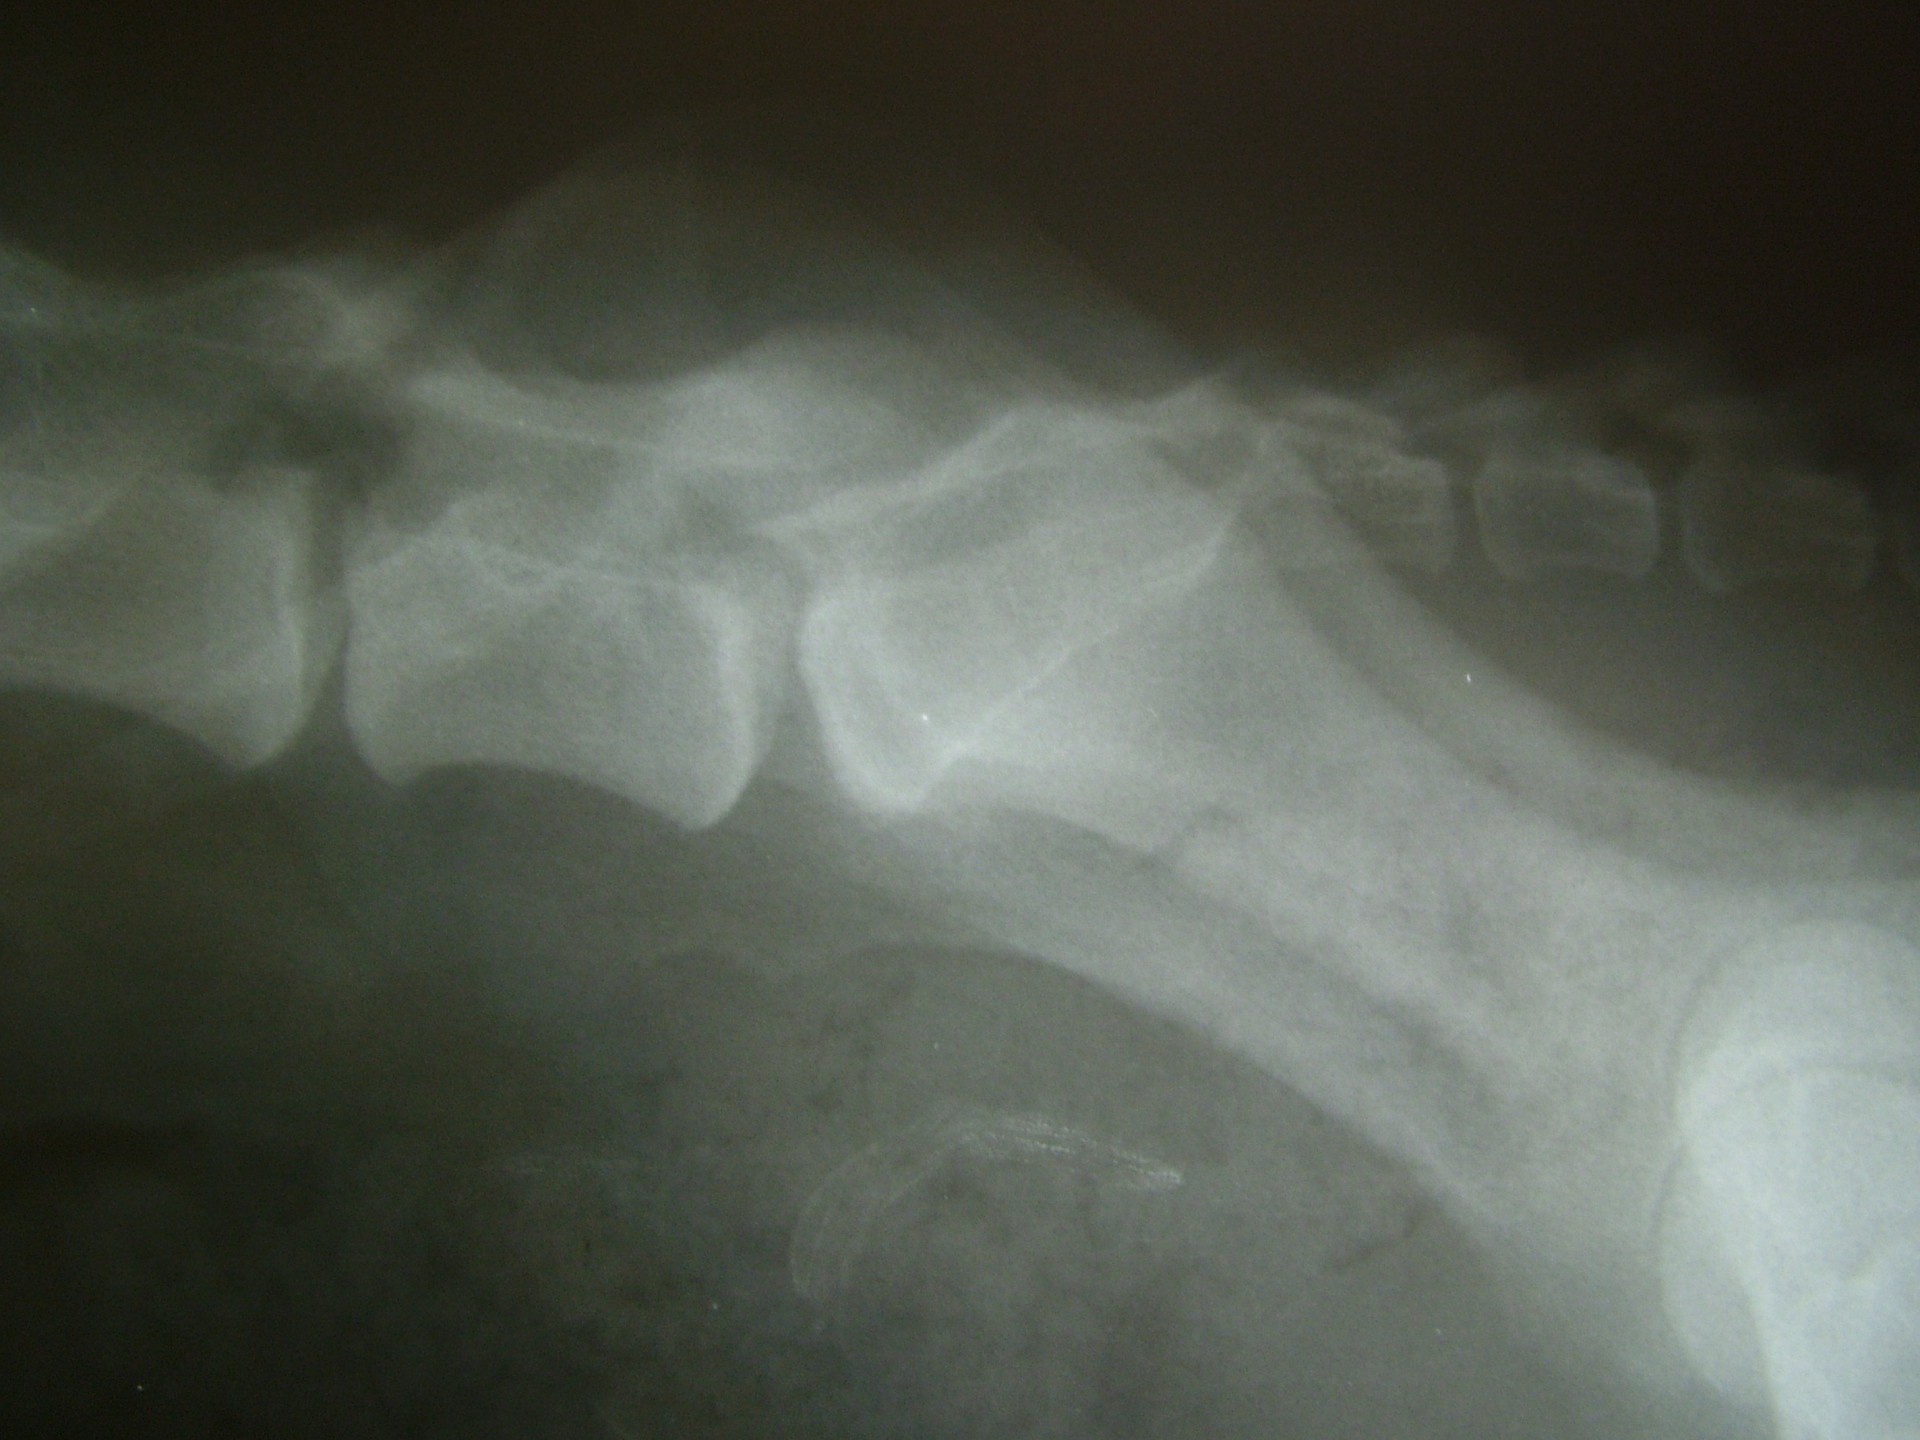

A C.E.C diagnosztikájának legfontosabb lépése a kórelőzmény megismerése után (hátulsó testfél gyengeség, rogyadozás, széklet-vizeletürítési problémák, fájdalom stb.) az alapos klinikai vizsgálat, mely során a gerinctájék fájdalmasságát, a hátulsó végtag reflexeit, a fájdalomérzet meglétét vizsgáljuk.Amennyiben a klinikai tünetek indokolják kiegészítő vizsgálatként elsősorban a röntgenvizsgálat jön szóba, mely során a gerincoszlop ezen szakaszáról oldalirányú felvételt készítünk.

Amennyiben a klinikai tünetek és az oldalirányú röntgenfelvétel alapján a C.E.C. alapos gyanúja felmerül további vizsgálatokkal kell kizárnunk egyéb gerincbetegségeket ill. megerősíteni a C.E.C. diagnózisát.

Az egyik ilyen vizsgálat a gerincfestés vagy myelographia, mely során a gerincvelőt körbevevő térbe (subduralis tér), az agy-gerincvelői folyadékba (liquor) röntgenkontraszt anyagot juttatunk és sorozatos felvételekkel ellenőrizzük annak áramlását. Ennek előnye, hogy a kontrasztanyag lefutása során az egyéb gerincszakaszok is kirajzolódnak, és ezek esetleges betegségeit is diagnosztizálhatjuk. A gerincoszlop hátsó szakaszáról 1db teljesen hajlított és 1 db teljesen nyújtott beállítású RTG felvételt készítünk. Ha a két felvétel között jelentős különbséget tapasztalunk a C.E.C. biztosan diagnosztizálható.A másik invazív diagnosztikai eljárás a durographia, mely során a röntgenkontraszt anyagot a durazsák körüli térbe (epiduralis tér) juttatjuk és így indirekt módon ábrázoljuk a gerincvelő esetleges összenyomatását. A vizsgálat során a kontrasztanyag telődési hiánya jelzi az összenyomatást és annak mértékét.A diagnosztika legmodernebb vizsgálati módszere az MRI vizsgálat, mely során altatásban, invazív beavatkozás nélkül kaphatunk átfogó képet a vizsgálni kívánt gerincszakaszról. Magyarországon állatorvosi diagnosztikai célra csak a Kaposvári Egyetem Diagnosztikai és Onkoradiológiai Intézetében működő berendezés használható.